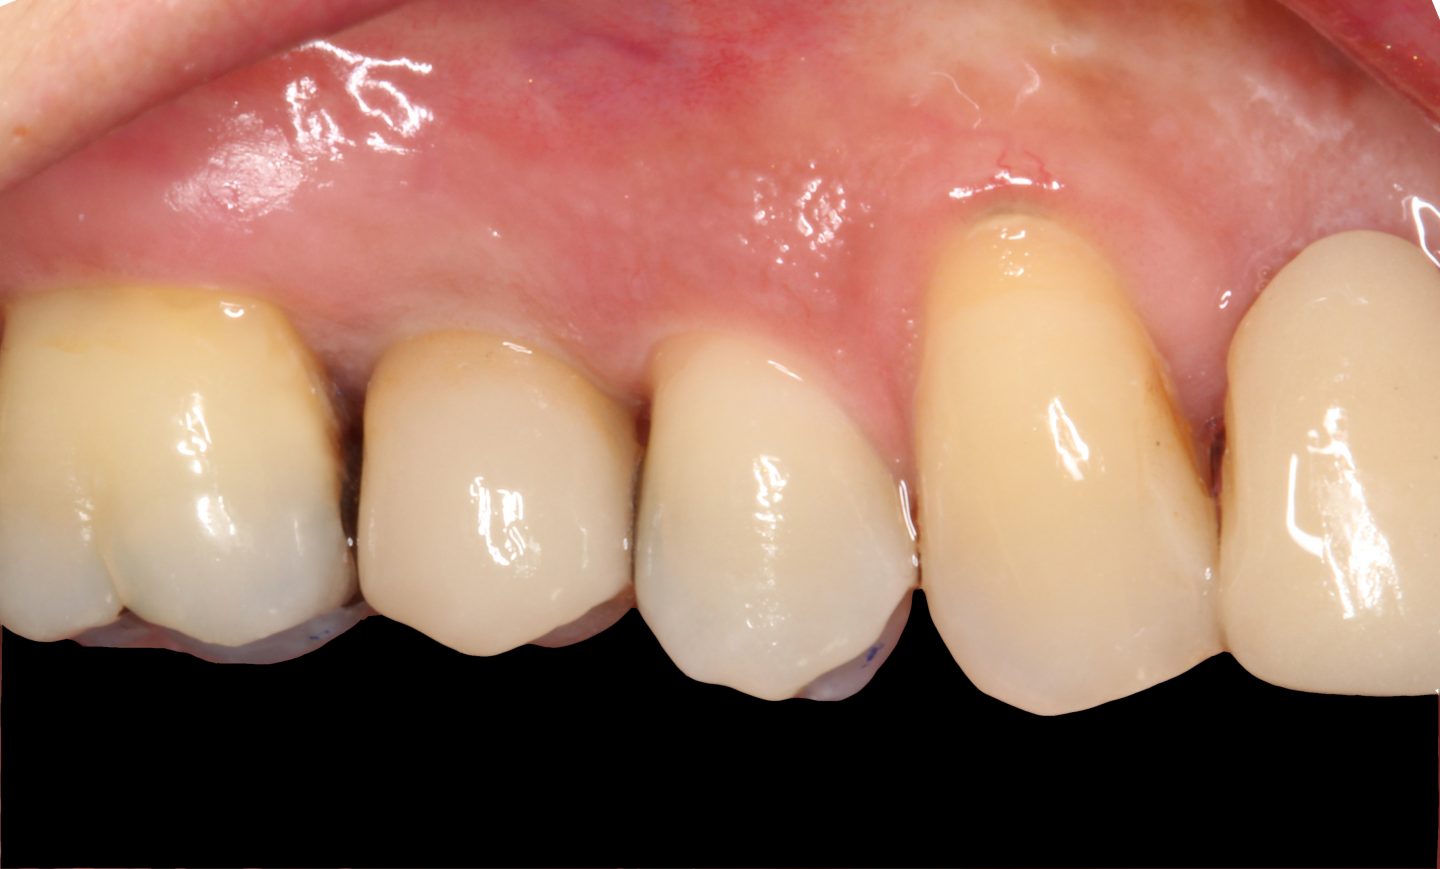

Einschrauben der CEREC-Implantatkrone

Nach einem Scan des Implantataufbaus im Mund wird die neue Implantatkrone gefertigt und eingschraubt.